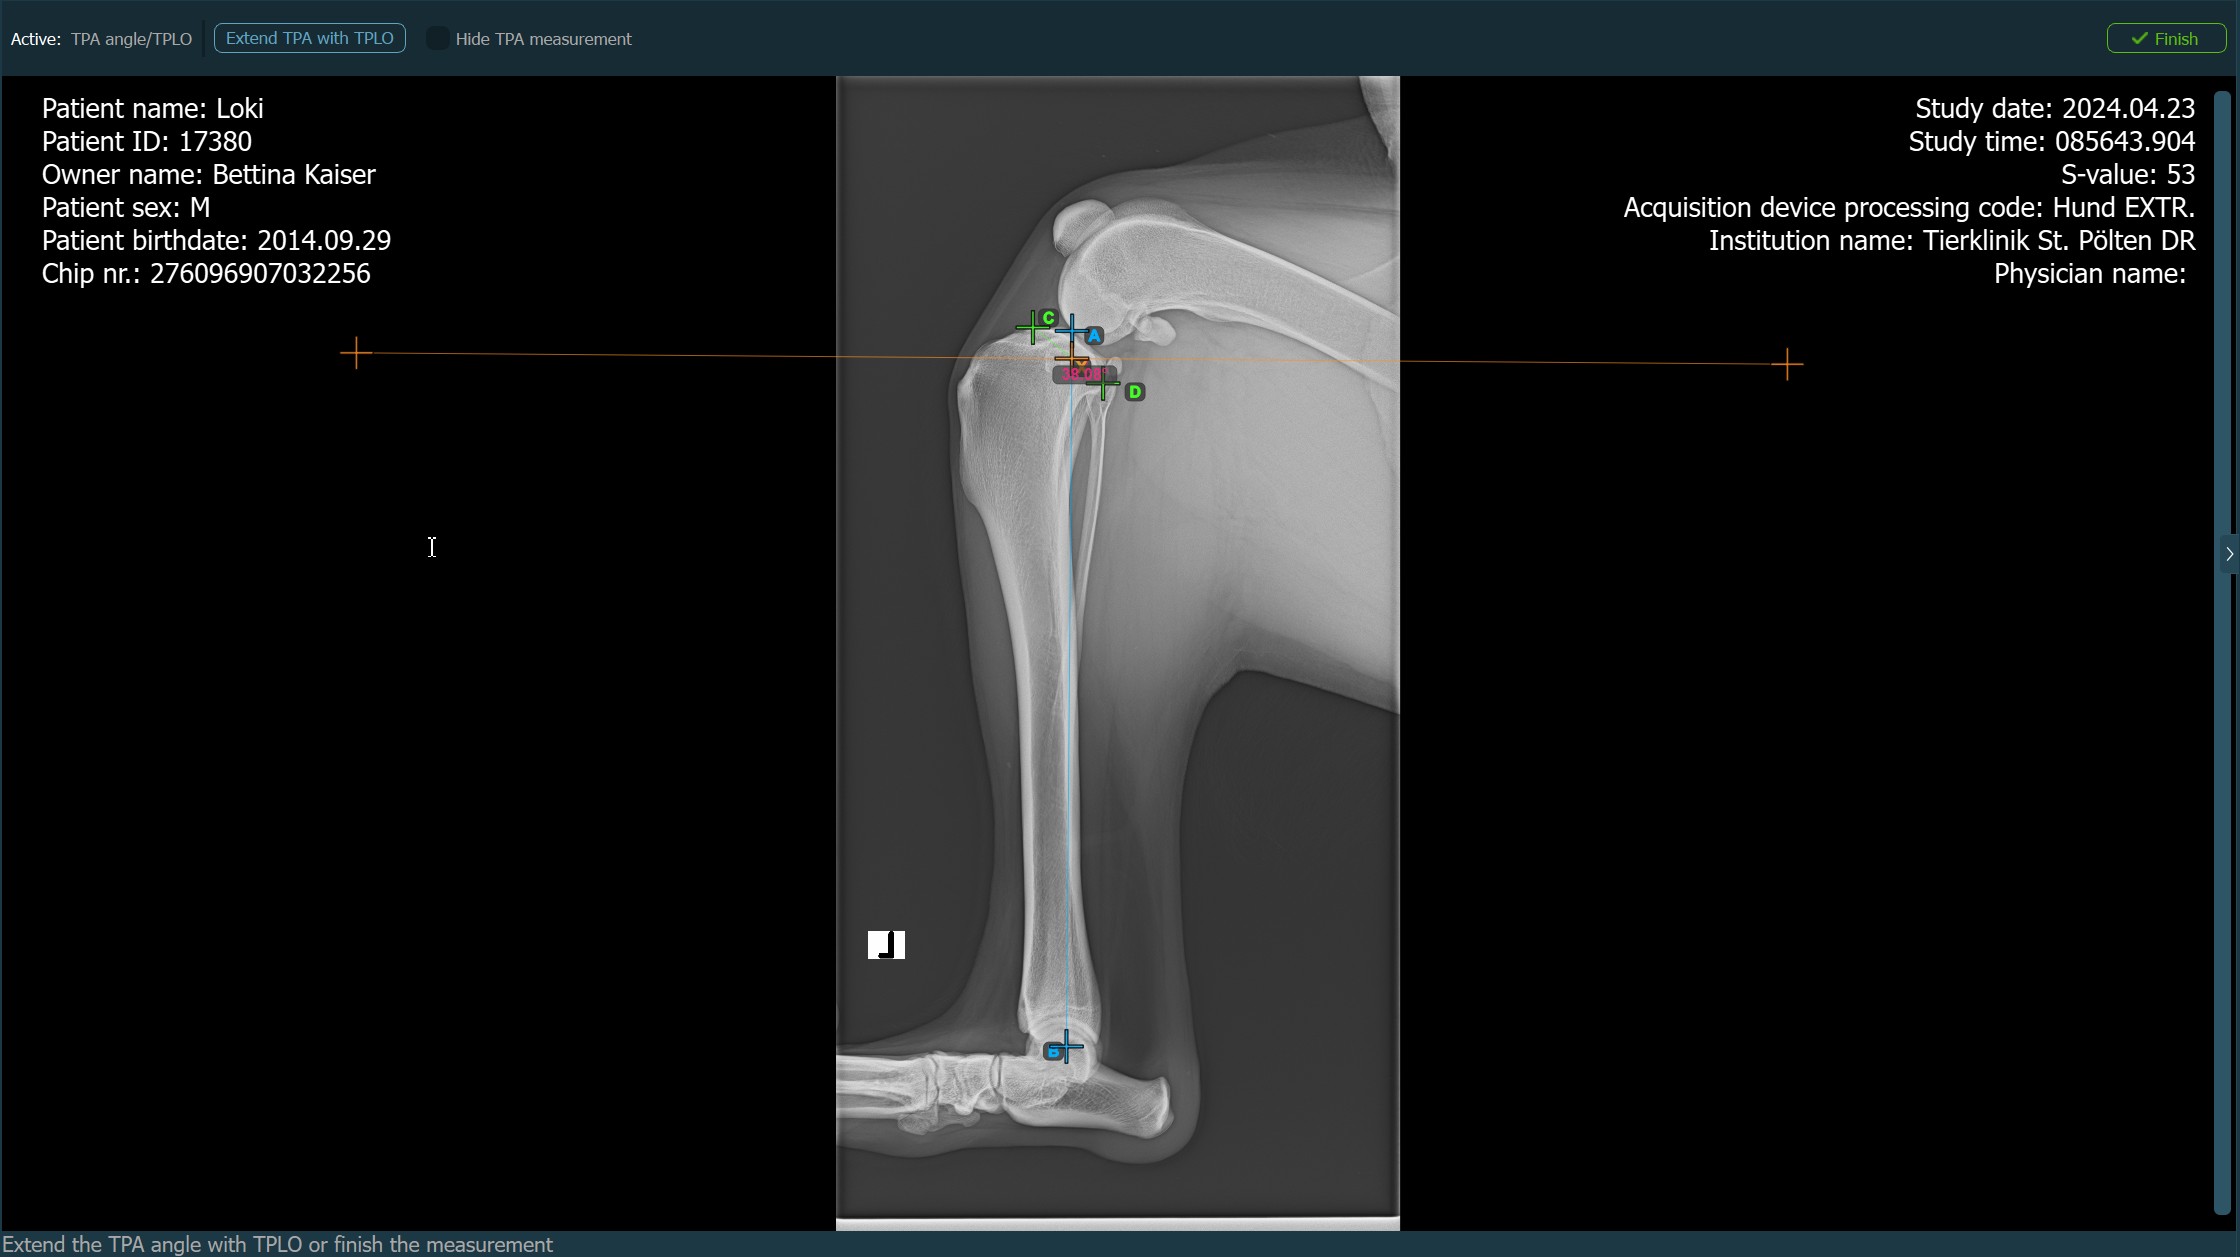

The image below depicts the usual placement of the Eminentia Intercondylaris point.

../../_images/image224.jpg

Continue by marking the midpoint of the Cochlea, located at the end of the tibial bone. The line created between the Eminentia Intercondylaris and the midpoint of the Cochlea represents the long axis of the tibia.

The image below depicts the usual placement of the midpoint of the Cochlea.